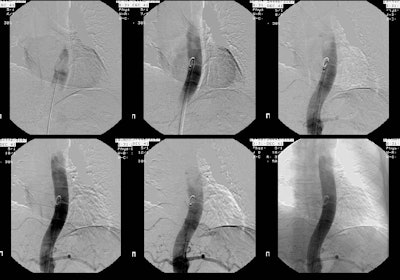

The CT scan demonstrated a low density mass in the left posterior costophrenic sulcus. A percutaneous biopsy was performed and on aspiration material with the consistency of "crank oil" was withdrawn. The fluid contained inflammatory cells, but no organisms. Surgical removal was recommended. Because of the possibility that the lesion may represent a bronchopulmonary sequestration, a pulmonary arteriogram was also performed.

The exam demonstrated no systemic arterial supply to the lesion. At histopathologic analysis the lesion was found to be a bronchogenic cyst.